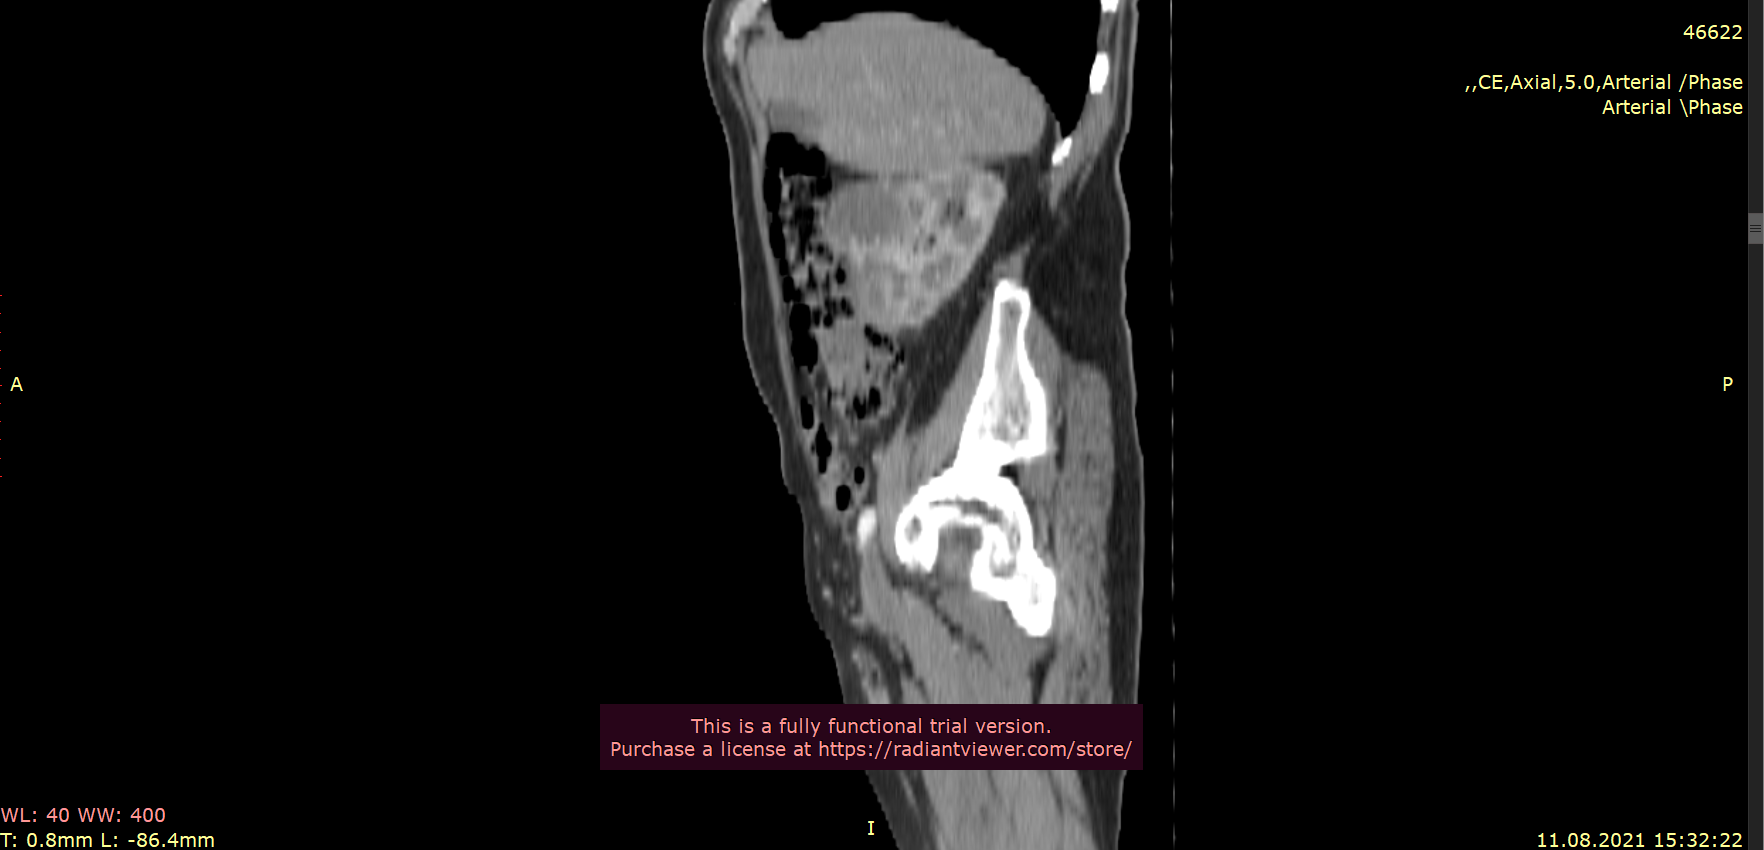

Права нирка типового положення, деформована за рахунок наявної неопластичної інфільтрації в передньо-латеральних відділах паренхіми середньо-нижнього сегментів з формуванням вузлового компоненту, що частково виходить за межі та деформує поверхню розміром 55*45 мм, структура гетерогенна з нерівномірним накопиченням контрасту, чітке відмежування від паренхіми – відсутнє. Нерівномірно сегментарно обтурован просвіт миски за рахунок інфільтрації на всьому протязі до рівня мисково-сечовідного сегменту.

Артерія – типового ретрокавального положення, без ознак обтурації просвіту, з наявною паравазальною інфільтрацією практично до рівня основи, інтактний відрізок до 17 мм від стінки аорти. Вена – шириною 25 мм, своєчасно контрастована, в ділянці воріт – втягнута в процес ураження, позаду та нижче на 11 мм від основної гілки від нижньої полої вени відходить гілка шириною до 3 мм, що васкуляризує нижній сегмент.

Висновок СКТ: Cr renis dextrae з тотальною інфільтрацією стінок миски, сформованим вузловим компонентом в передніх відділах середнього сегменту, інфільтрація поширюється вздовж стінок ренальної артерії, субтотально.